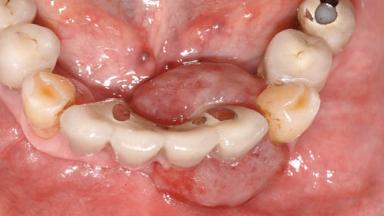

Peripheral Giant-cell Granuloma Associated with Peri-implant Tissues

Giant-cell granulomas (GCG) of the jaws are benign reactive lesions of unknown etiology, unrelated to giant-cell tumors (osteoclastomas), which are defined as benign but locally destructive and aggressive neoplasms (Jundt and coworkers 2005). Depending on their localization at the initial diagnosis, GCG are dived into central (CGCG) and peripheral (PGCG) types. CGCGs occur within the jawbones and appear as unilocular or multilocular radiolucent lesions. The incidence in the general population is very low. They are more commonly found in the mandible, mainly in children and young adults—patients are generally younger than 30 years—and have a greater incidence in females (Heithersay and coworkers 2002). The clinical behavior of CGCGs varies from slowly growing asymptomatic swellings to aggressive lesions that may result in pain, cortical perforation of the affected jaw site, and root resorption (de Lange and coworkers 2007).

# of Teeth 10

# of Implants 5

Type of Implants One-Piece